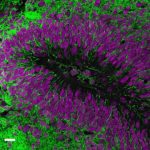

Study: Human brain cell transplant offers insights into neurological conditions — (Details)

In the new study, led by Imperial College London in collaboration with a group from the University of Cambridge, researchers transplanted human brain...